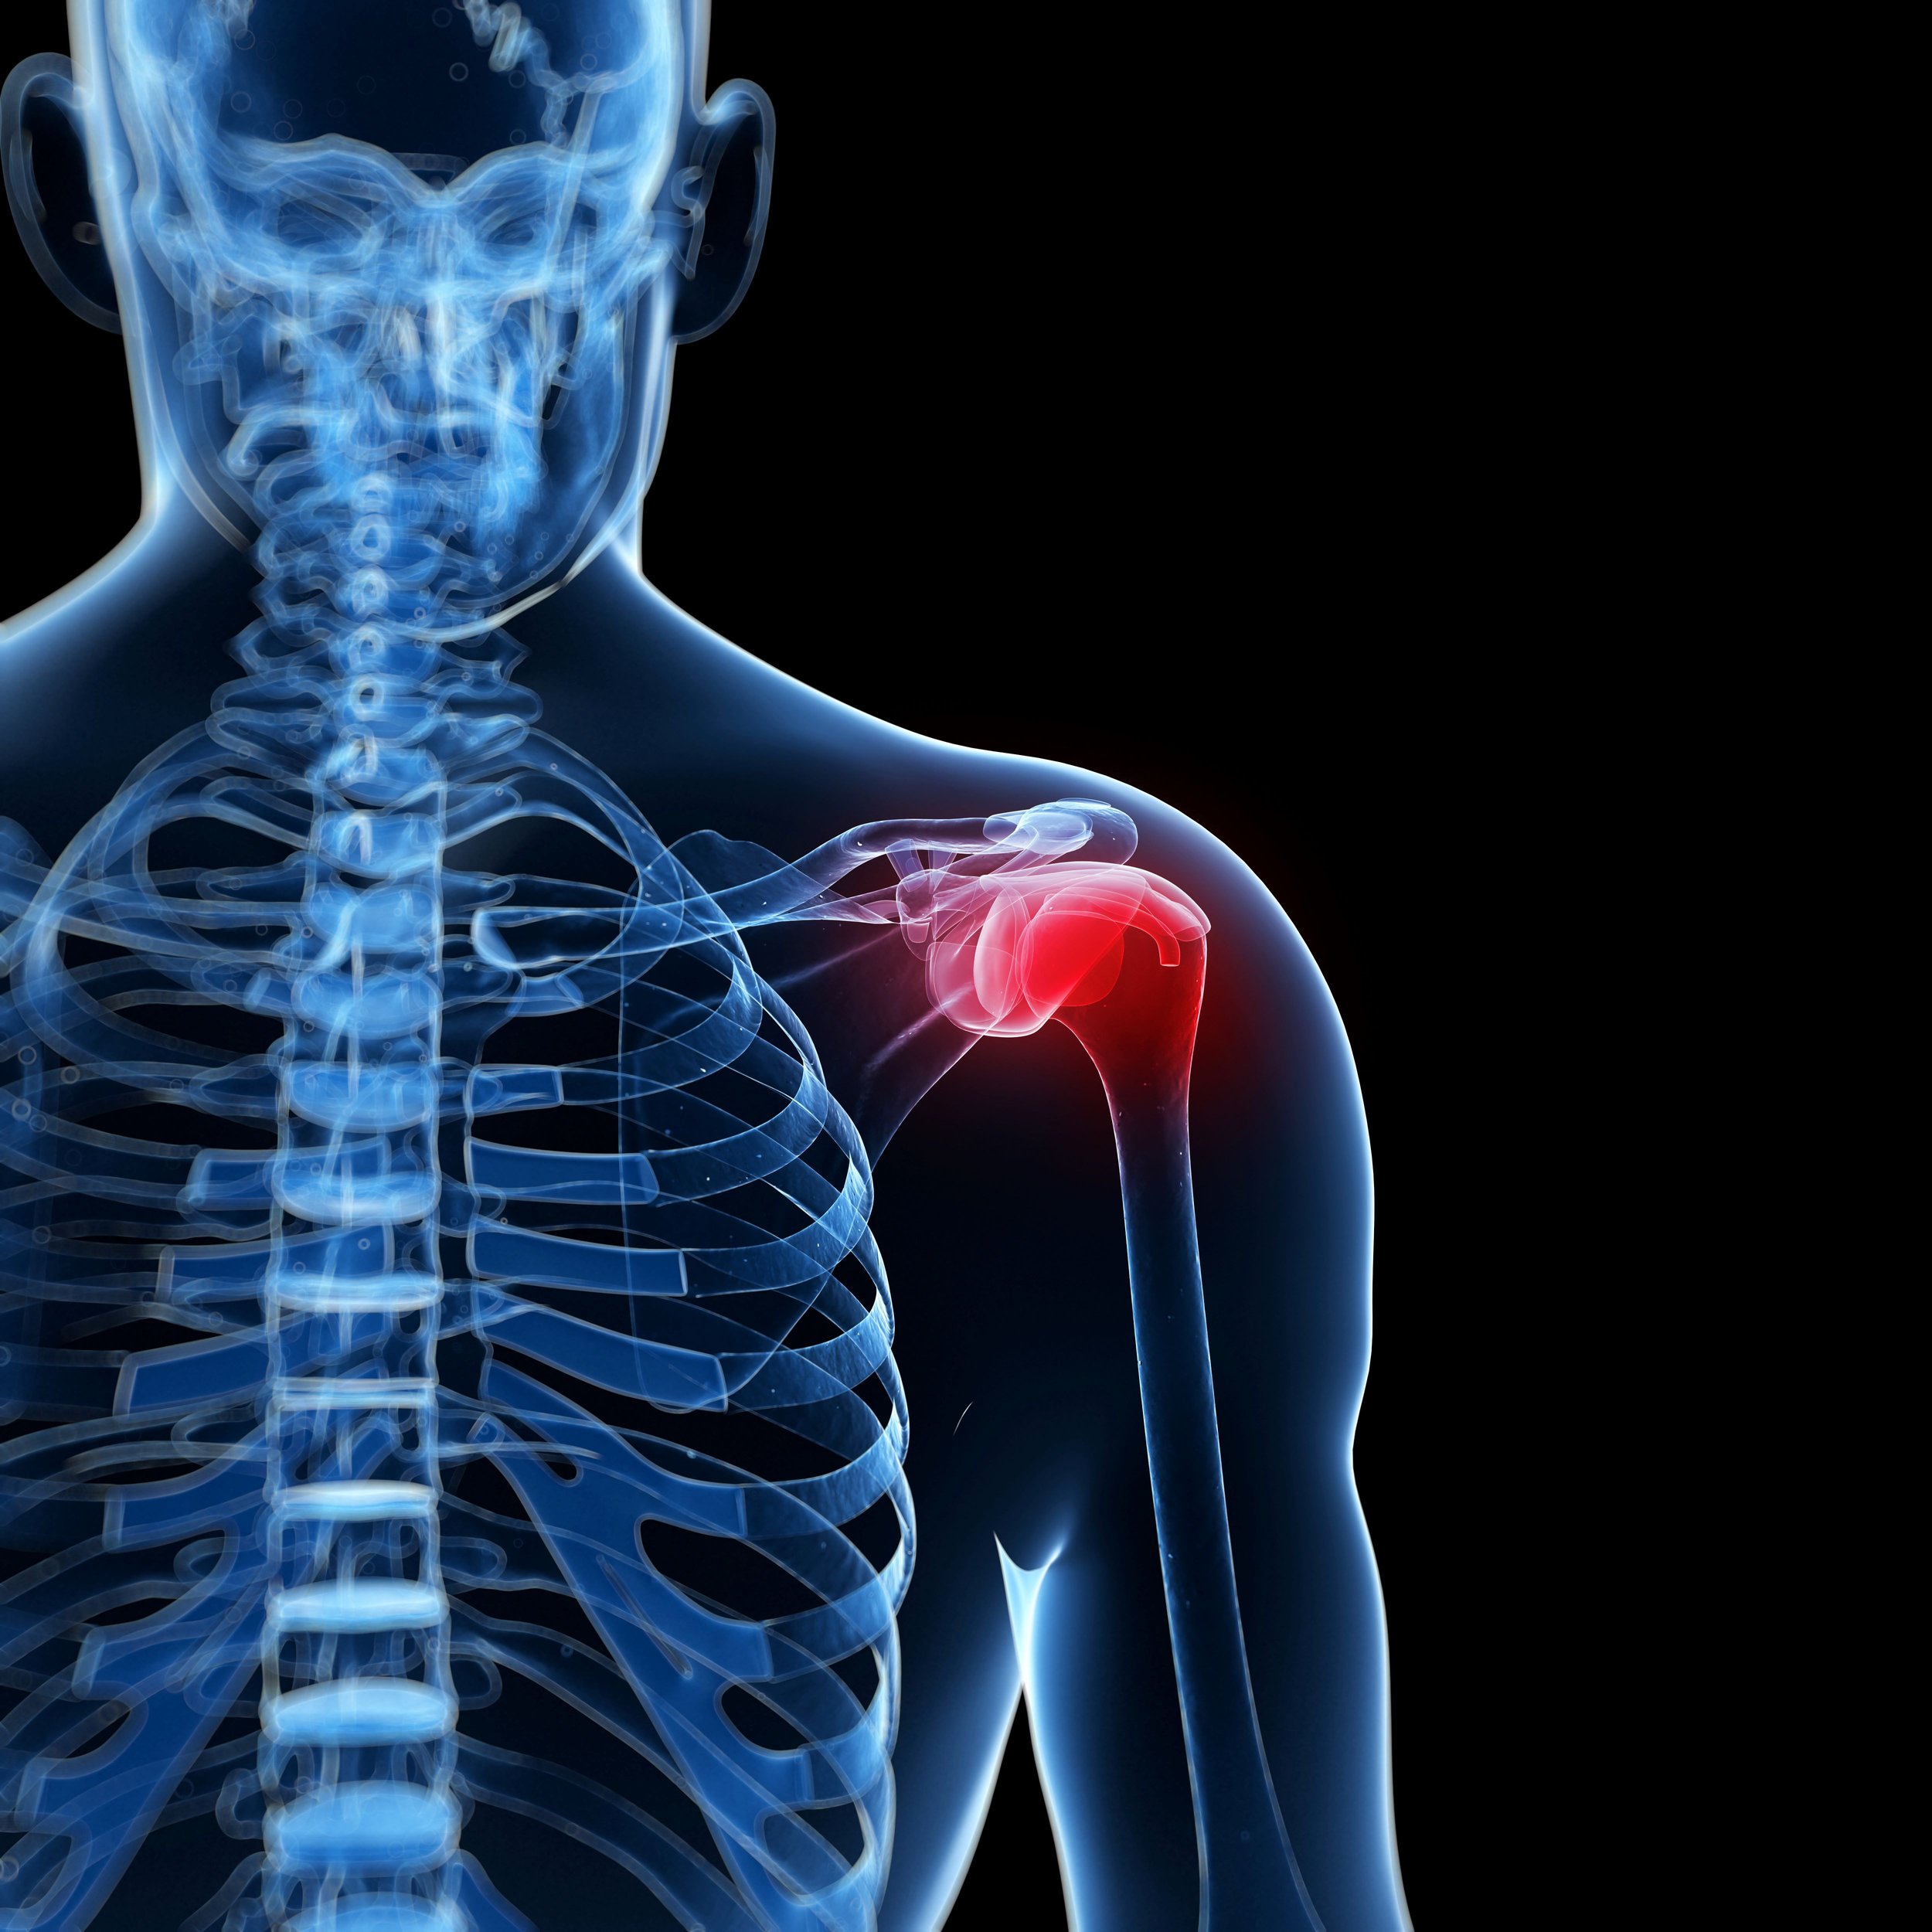

Combining Acupuncture and Physical Therapy for Frozen Shoulder

Explore how adding acupuncture to physical therapy enhances pain relief and range of motion for patients with frozen shoulder, based on a 2024 systematic review and meta-analysis.

Acupuncture for Frozen Shoulder

Learn what causes frozen shoulder, common trigger points that refer pain the shoulder and how to treat frozen shoulder with acupuncture.